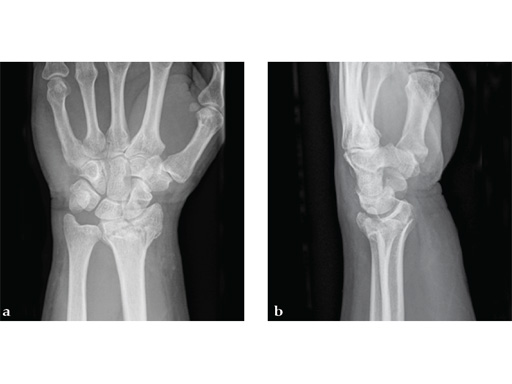

Case 1: A 62-year-old man fell on his outstretched left hand while playing tennis, sustaining an intraarticular fracture of the distal radius, Mller AO Classification 23-C3.2.

Case provided by Renato Fricker, Bruderholz, Switzerland

Case 2: A 44-year-old man sustained polytrauma following a car accident. Among his injuries was a distal radial fracture, Mller AO Classification 23-C1.

Case provided by Vitezslav Ruber, Brno, Czech Republic